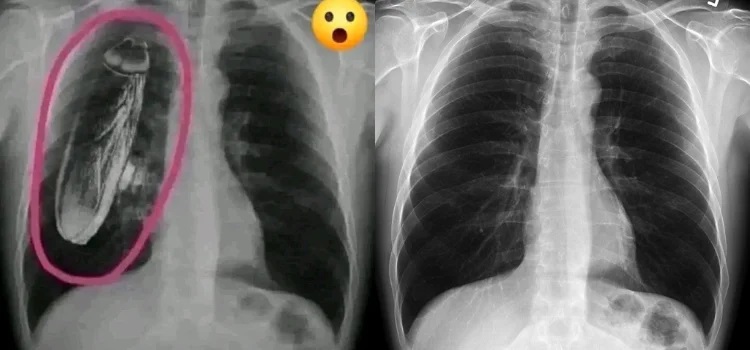

Fotoğrafta dijital müdahale var

İddiaya eklenen fotoğraf tersine görsel arama yöntemiyle arandığında, “hamam böceğinin” fotoğrafa sonradan eklendiği anlaşılıyor. Fotoğrafın aslı standart bir göğüs röntgeni.

İki görsel karşılaştırıldığında, böceğin sonradan eklendiği de görülüyor.